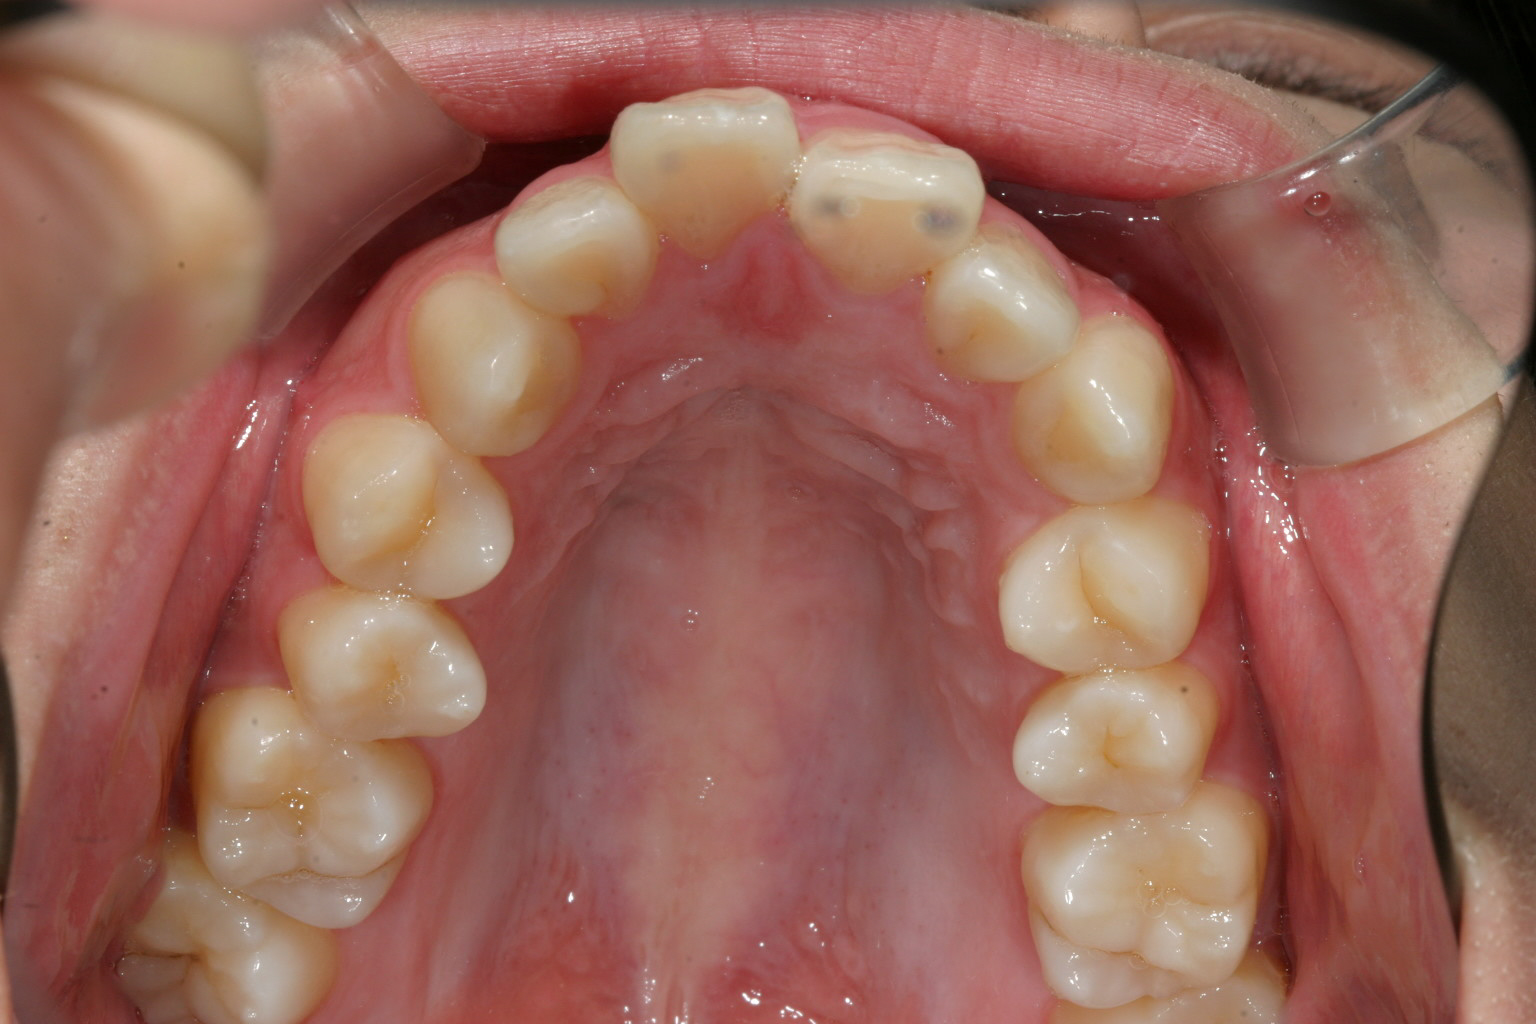

歯列がV字になっている為犬歯と犬歯の幅が狭く前歯が前に飛び出してます。

下顎はV字が特にひどく小臼歯あたりが狭くなっています。